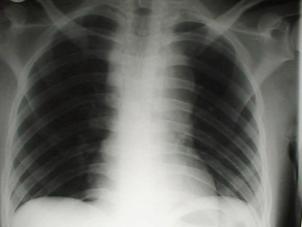

TRAUMATISME TORACICE

Emfizem subcutanat

Emfizem subcutanat Emfizem subcutanat

Aspect radiologic Imagine CT

Pneumotorace sufocant bilateral Pneumotorace sufocant stang

Hemotorace stang masiv Hemotorace stang masiv

Hemotorace

drept masiv  Hemotorace stang

Imagine CT Radiografie efectuata in ortostatism

Hemotorace drept  Hemo-pneumotorace stang

Radiografie efectuata in clinostatism

Hemo-pneumotorace stangDetaliu Fracturi costale multiple.Volet costal drept

Fracturi costale multiple  Hemitorace drept strivit